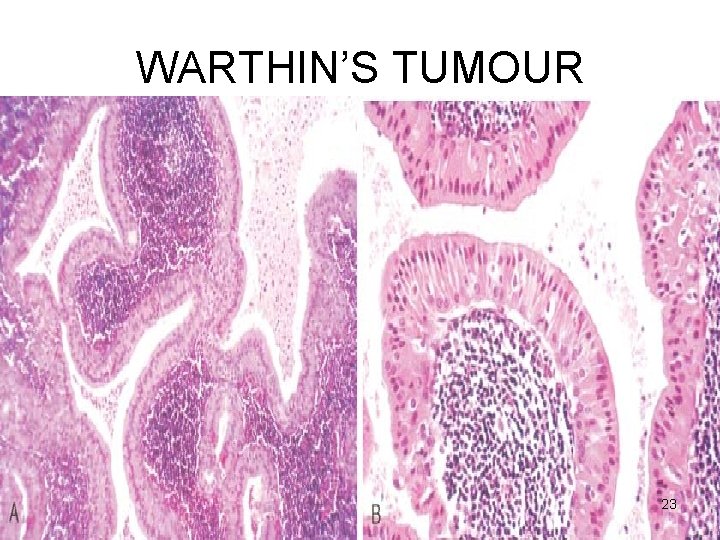

WARTHIN’S TUMOUR Microscopy Cystic spaces - Narrow / cleft-like CYSTADENOMA Lining – double-layered epithelium – infoldings PAPILLARY • Inner (lumen) – palisade of columnar cells with abundant finely granular eosinophilic cytoplasm (oncocytic) • Outer (below the first) – cuboidal / polygonal Stroma - dense lymphoid tissue (germinal centres + ) LYMPHOMATOSUM 22

WARTHIN’S TUMOUR 23